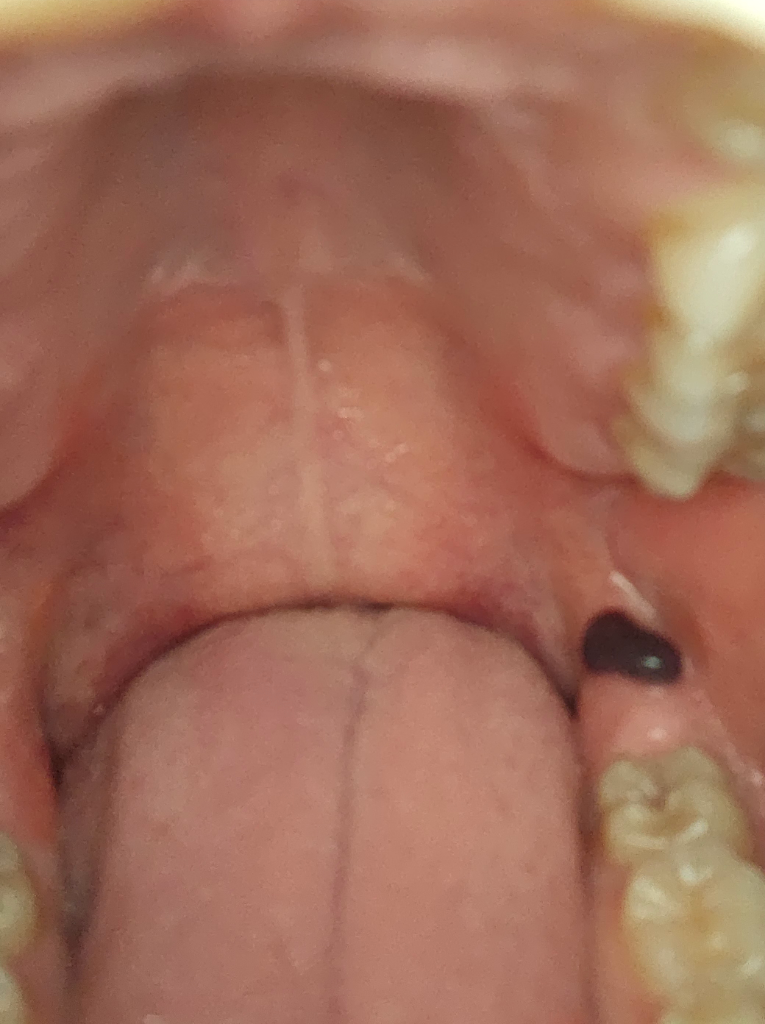

잇몸에 피가 고인 상황일 가능성이 높아보입니다.

사진의 소견을 통해서 볼 때에는 피고름이 찬 것이며 보통은 시간이 경과하면서 스스로 호전되는 경과를 보이긴 하지만 혹시 모르기 때문에 이비인후과적으로 진료를 받아보시고 적절하게 치료를 하시는 것이 안전할 것으로 사료됩니다.